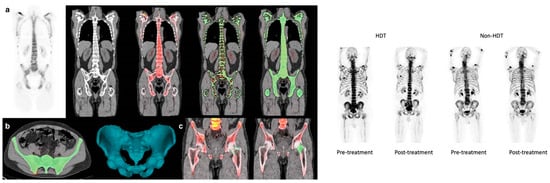

In a recent study, the aim was to compare the effects of treatment—specifically, conventional standard-dose chemotherapy (CDC) versus HDC followed by autologous stem cell transplantation (HDC/ASCT)—on the overall brain glucose metabolism of MM patients [46]. The researchers employed a comprehensive brain [18F]FDG PET measurement approach for this purpose, providing an evaluation of changes in 18FDG metabolism throughout the whole brain (Figure 9) [46]. After treatment, a notable reduction in the GSUVmean (global standardized uptake value mean) was observed in the supratentorial brain and cerebellum of patients who underwent HDC/ASCT (p-values < 0.05) (Figure 9) [46]. Conversely, there were no statistically significant GSUVmean changes after treatment in patients who received CDC (Figure 9). The scientists concluded that a significant decrease in [18F]FDG uptake in the brain after treatment was only observed in patients who received HDC/ASCT [46]. This observation might suggest a tendency for chemo brain to be more prevalent in cases involving HDT [46].

Figure 9.

The left figures depict the use of designated regions of interest (ROIs) for the supratentorial and cerebellum areas within the brain of a multiple myeloma patient. The separation of the supratentorial region from the cerebellum was achieved using the tentorium cerebelli as a reference point. Patients (a,b) received high-dose therapy, whereas patient (c) received conventional chemotherapy, resulting in fewer changes in brain [18F]FDG uptake compared to patients (a,b).

Certain research teams have recently proposed using CT-based segmentation to analyze the uptake of radiotracers in the bone marrow and the overall bone structure of myeloma patients as an alternative to concentrating solely on specific osteolytic lesions [23] (Figure 10 and Figure 11). These approaches have demonstrated a high level of reproducibility [23] (Table 1). However, the clinical significance of these methods still needs to be investigated further [23]. This method has recently been used by the Penn–Odense group to assess the uptake of [18F]FDG in the context of dual-time-point imaging (Figure 12) [35]. Pre-treatment [18F]FDG PET/CT scans from 36 patients with MM were collected [35]. These scans were conducted at 1 and 3 h after the injection of the tracer. A segmentation and quantification of whole-bone marrow (WBM) [18F]FDG uptake was performed using a threshold algorithm utilizing Hounsfield units obtained from CT data [35]. The patients were split into two treatment groups: one received non-HDT, and the other received HDT with ASCT. The international response criteria were utilized to assess the treatment outcomes for each multiple myeloma patient. In the group that underwent HDT, there was a notable increase in WBM [18F]FDG uptake among patients who responded poorly to treatment (Figure 12) [35]. The median value escalated from 1.31 (with an interquartile range, IQR, of 1.13–1.64) after one hour to 1.85 (IQR: 1.45–2.10) at the three-hour mark, illustrating this increase [35]. The calculated median percentage alteration ranged from 6.10% to 50.73% (IQR: 23.47–46.4; p = 0.003). In contrast, there was no apparent change in uptake for patients exhibiting a complete response (p = 0.24) (Figure 12). A similar pattern was observed in the non-HDT group [35].

Figure 12.

The upper row of images includes a PET scan (A), a merged PET/CT scan (B), and a combined PET/CT scan with a region of interest (ROI) applied before the use of the morphological closing algorithm (C) in a patient with multiple myeloma (MM). In the bottom row, the left-hand side images display PET scans of an MM patient classified in the poor response to treatment group, captured at 1 h (D) and 3 h (E). In this patient, the overall bone marrow [18F]FDG uptake escalated from 0.89 (D) to 2.31 (E), reflecting a percentage change of 158.15%. On the right-hand side of the bottom row, the images present PET scans of an MM patient from the complete response group, taken at 1 h (F) and 3 h (G). In this patient, there was a slight reduction in the overall bone marrow [18F]FDG uptake, dropping from 0.83 (F) to 0.82 (G), with a percentage change of −0.79%. Note that the second decimal number is rounded up. PMID: 33224622, PMCID: PMC7675111, Free Access.